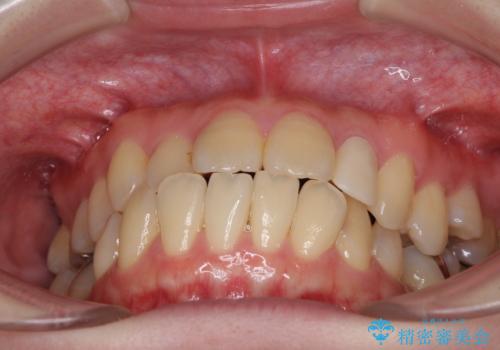

- 下顎の歯が舌側に倒れていることと、前歯の咬み合わせの不具合を気にして来院された患者様です。

受け口傾向の口元であるため、下顎左右小臼歯各1歯を抜歯して歯列を整えることとしました。

前歯には治療中の仮歯が装着されていたため、矯正治療後にオールセラミッククラウンにて補綴治療を行うこととしました。